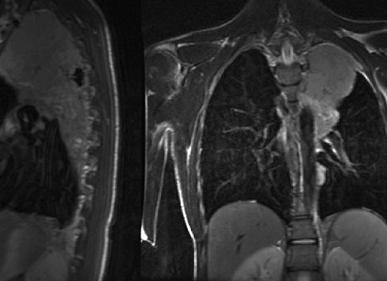

Магнитно-резонансная томография средостения и органов грудной клетки является современным диагностическим методом, позволяющим определить контур и структуру легких, сердца, кровеносных сосудов и лимфатических узлов.

МРТ полости грудной клетки показывает только сильно проявляющиеся патологические изменения: воспаления, новообразования, повреждение органов и тканей и др.

Основное преимущество МРТ — это возможность отображения изменений во всех тканях и органах. Изображение на мониторе томографа покажет внутреннее содержимое грудной полости. Можно четко рассмотреть здоровые органы и ткани, патологически измененные. Структуры грудной клетки изображаются послойно, что позволяет с высокой точностью проанализировать размеры нужного участка. МРТ даже позволяет определить биохимические процессы в клетках и дифференцировать начальную стадию онкологических процессов.

С помощью МРТ возможно оценить состояние всех тканей и органов грудной клетки, средостения, кровеносного питания, плевры и стенок полости. А также томограф создаёт высокую детализацию работы сердечно-сосудистой системы, что даёт возможность специалисту провести оценку её работы.

При помощи данной процедуры специалист получает подробное изображение органов грудной полости, а также ее стенок, средостения, плевры с сосудами и сердцем, причем все это под разными углами. Есть возможность проводить последовательные съемки не только сердца и сосудов, но и сердечных клапанов.